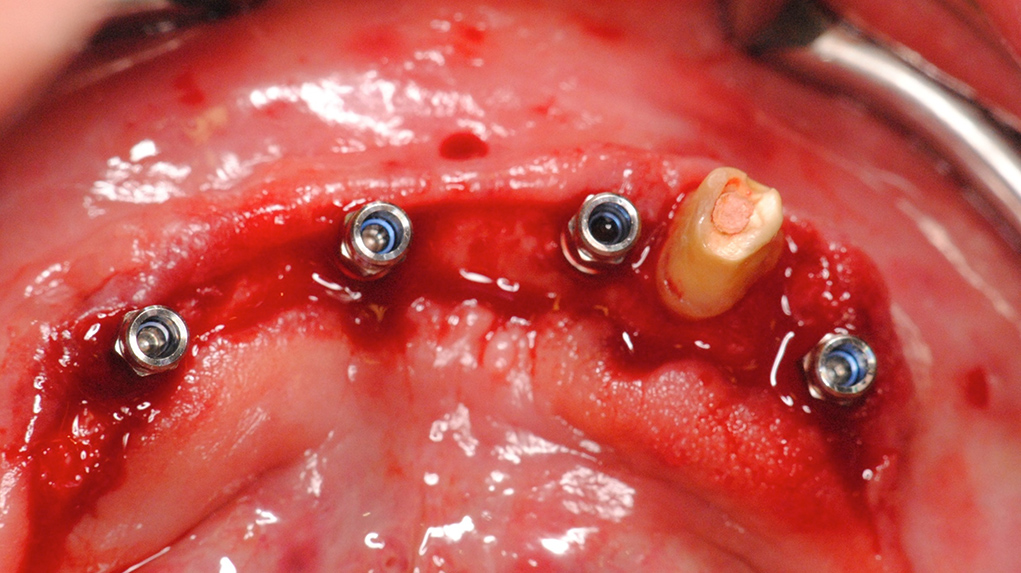

View DetailComputer guided implantation with CAD/CAM primary structure and removable denture

Contributed by Dr. Frank Spiegelberg on Jun 16 2014

In the following case a backward planning with the SimPlant software is drawn up based on a scanning template and with DICOM data from the cone beam with the aim to create a drilling template prior to...